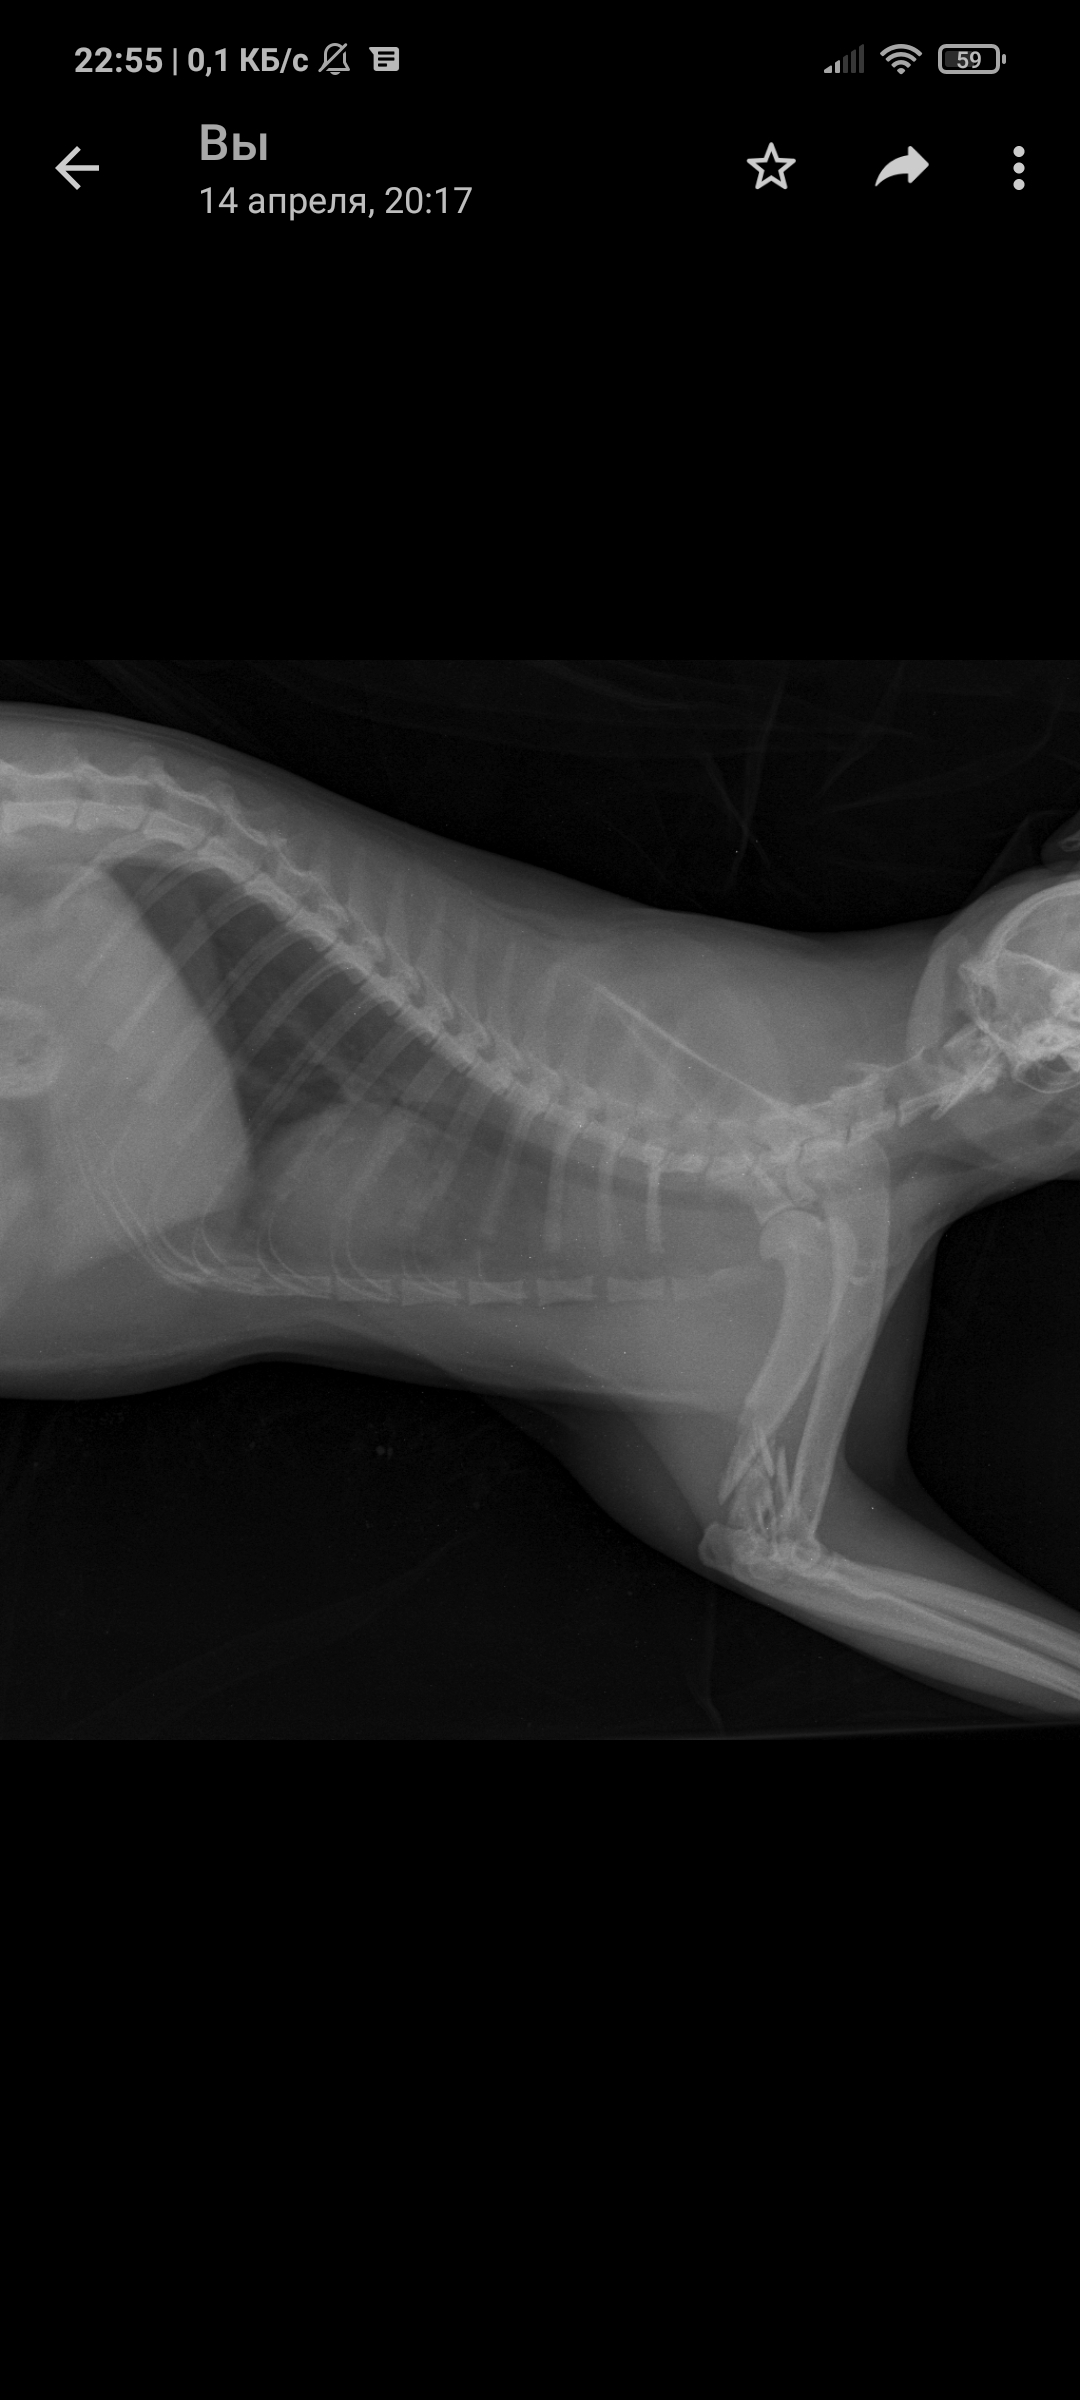

Так уж получилось что я ветеринарный врач, работаю в интенсивной терапии - принимаю и лечу самых тяжелых животных. На днях ближе к ночи прибегает женщина с котом, который шлёпнулся перед ней на улице. При осмотре выясняется что кот в шоке - лежит на боку, без давления, температуры, у него сломаны передние лапы, лицо, пневмоторакс и немного жидкости в брюшной полости (вероятно кровь). Женщина оставляет двадцатку на первые сутки и идет искать хозяина, кот помещается в стационар для стабилизации состояния. Всю ночь я ебусь с этим котом, вывожу его из шока, спускаю ему пневмоторакс, грею, обезболы льются рекой, к утру кот похож на кота, а не на покойника - начал садиться, ползать, полизал еду.